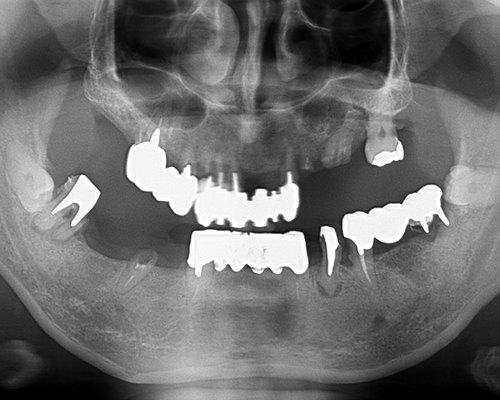

| 施術内容 | 前歯は虫歯や歯の動揺が大きく、奥歯も虫歯や歯根破折のため保存困難。左上1本以外抜歯し、骨が足りない部位は骨増生を行いインプラント治療へ。通常の入れ歯と違いインプラントを固定源とするため、安定性がかなり高いです。(治療期間中は入れ歯を使用) |

|---|---|

| 治療期間 | 約1年半(抜歯後治癒期間含) |

| 治療費 | 約280万円(プラスチック前装冠) |

| 副作用・リスク | インプラント治療は手術を伴います。腫れや痛みが少なくなるよう努力をしておりますが、多少の腫れや痛みが出ます。しかし、痛み止めで抑えられる程度ですのでご安心ください。 |

※表示は全て税込表示です。